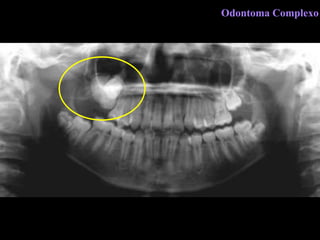

Odontoma Complexo

C l í n i c a Malformação de tecidos dentários. Região de pré-molares e molares, ambos os maxilares. Retenção de dentes. Preferência 1º e 2° décadas. Odontoma Complexo

R a d i o l o g i a  Área radiopaca de limites definidos  Banda radiolúcida periférica Pode se associar a um dente não irrompido Odontoma Complexo

D i a g n ó s t i c o  D i f e r e n c i a l Fibro-odontoma ameloblástico Osteoesclerose Lesões cementárias  Odontoma Complexo